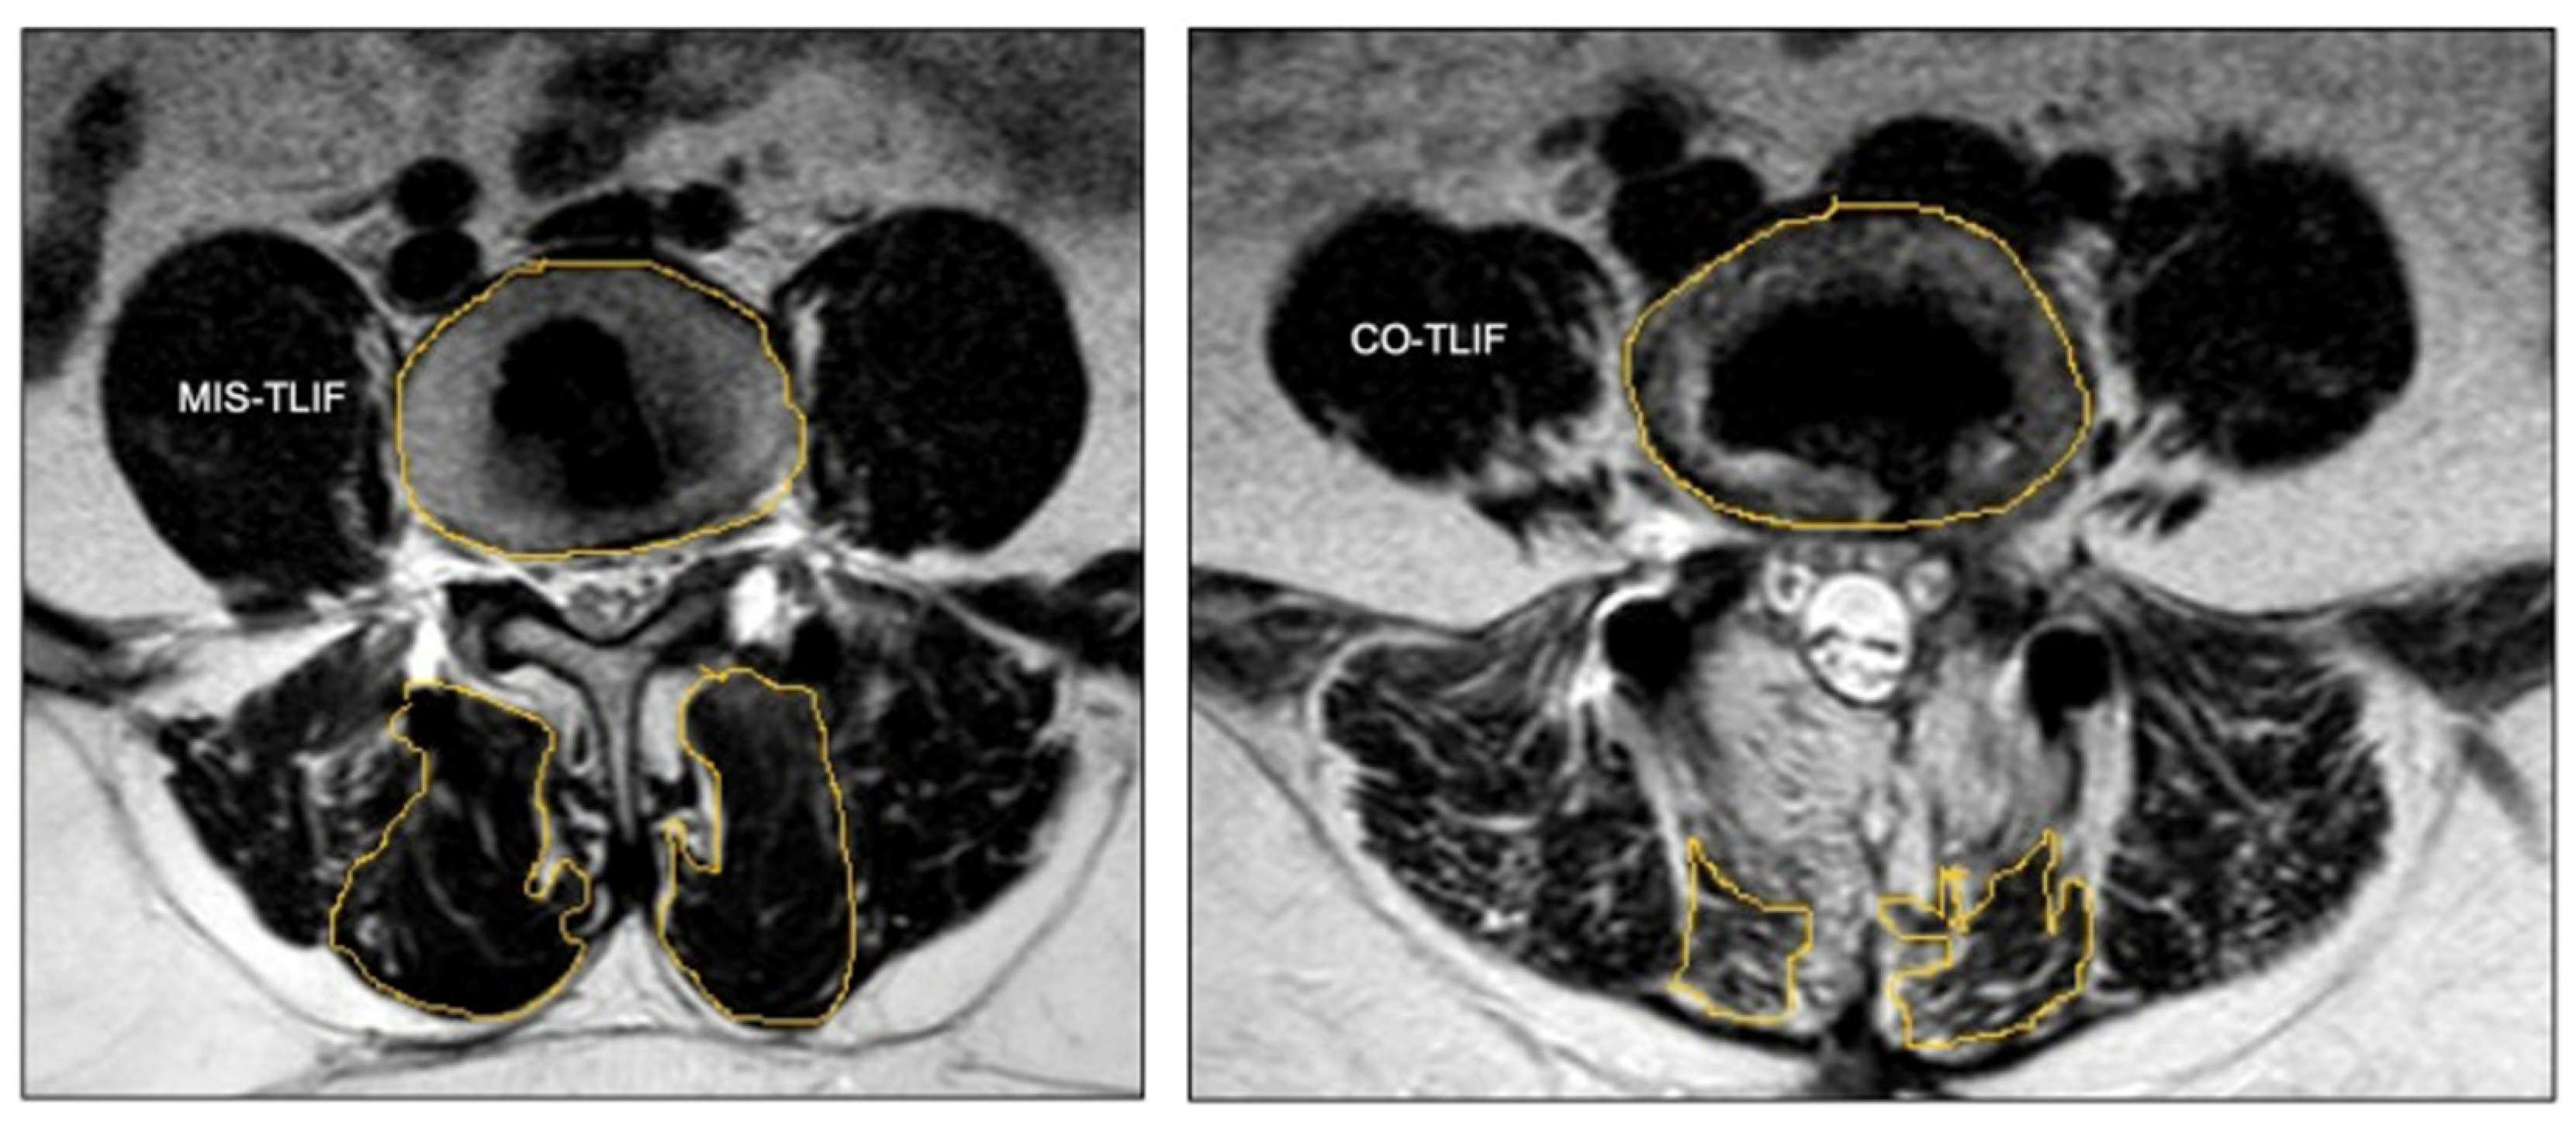

- Fu, C.J.; Chen, W.C.; Lu, M.L.; Cheng, C.H.; Niu, C.C. Comparison of paraspinal muscle degeneration and decompression effect between conventional open and minimal invasive approaches for posterior lumbar spine surgery. Sci. Rep. 2020, 10, 14635. [Google Scholar] [CrossRef] [PubMed]

- Tabarestani, T.Q.; Salven, D.S.; Sykes, D.A.W.; Bardeesi, A.M.; Bartlett, A.M.; Wang, T.Y.; Paturu, M.R.; Dibble, C.F.; Shaffrey, C.I.; Ray, W.Z.; et al. Using Novel Segmentation Technology to Define Safe Corridors for Minimally Invasive Posterior Lumbar Interbody Fusion. Oper. Neurosurg. 2023. [Google Scholar] [CrossRef] [PubMed]